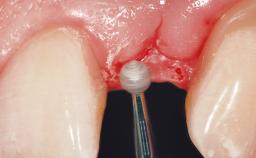

Late Flapless Placement of an Implant in a Maxillary Left Central Incisor Site

A 39-year-old male patient presented with a chief complaint of discomfort and gingival discoloration around his maxillary left central incisor. He was in good general health and was a non-smoker. His past dental history was significant because of the traumatic fracture of tooth 21 in a sporting accident at age 13. Initial dental treatment included endodontic therapy and a full-coverage restoration. The patient became symptomatic 5 years later, when structural failure of the tooth resulted in the dislodgment of the crown. Endodontic retreatment, apical surgery, and post-and-core restoration were performed.

Bone Augmentation Horizontal|Staged

Augmentation Materials Xenogenous|Membrane

Soft Tissue Grafting Simultaneous

Bone Volume Deficient horizontally, requiring prior grafting